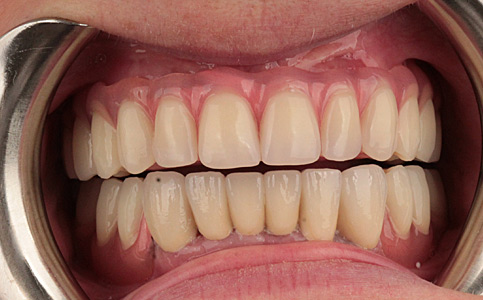

Przykład pełnej rehabilitacji protetycznej obejmujący leczenie biologiczne, uzupełnienie braków zębowych implantami oraz korony pełnoceramiczne w łuku górnym i dolnym. Spektakularna metamorfoza uśmiechu wykonana przez zespół Centrum Stomatologii i Ortodoncji FRESHmed odmieniła życie Pacjenta dodała pewności siebie i sprawiła, że z chęcią się uśmiecha.